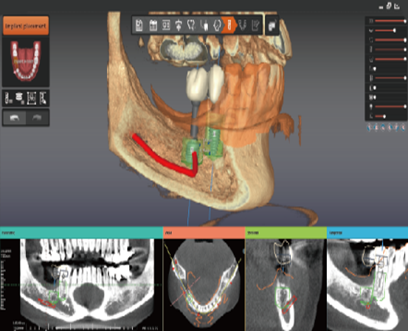

Our research center is being reborn as a global leading digital dentistry research Institute with its outstanding R&D talent on core technologies in the 3D Imaging field as well as dental solution field. 3DII continuously invests in R&D and conducts activities to secure and apply new technologies for AI, Big Data, Cloud, and Digital Transformation.